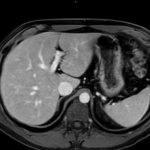

L’IRM abdominale est d’une grande utilité lorsqu’une analyse très fine des organes situés au sein de la cavité abdominale est nécessaire et que certaines lésions ne sont pas visibles avec les autres techniques d’imagerie (radiographie, échographie ou scanner).

Elle permet de réaliser des images en coupe ou acquisitions 3D apportant non seulement des informations sur l’anatomie de l’organe mais également sur la viabilité de certaines lésions et d’évaluer ainsi la réponse au traitement de façon plus précise.

Ce type d’exploration s’intéresse au foie, aux surrénales, aux reins, au pancréas, à la rate et au péritoine

– recherche d’une surcharge en fer du foie,

– quantification d’une stéatose, suivi des fibroses intra-hépatiques,

– cartographie des lésions cancéreuses et suivi de leur réponse sous traitement,